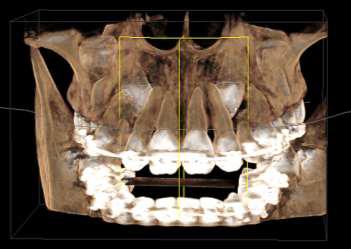

RECONSTRUCCION 3D DE LA ZONA A ESTUDIAR

Las reconstrucciones tridimensionales nos permiten una visualización detallada y precisa de las estructuras vecinas a la pieza retenida, superando las limitaciones 2D de las radiografías convencionales, también ayudara en este caso para la planificación quirúrgica y posterior tratamiento de ortodoncia.

En este caso podemos observar una lesión de diámetro considerable de bordes corticalizados y forma irregular proyectada en el maxilar superior en el cuadrante 1, que se extiende desde distal de la pieza 1.1 hasta distal de la pieza 1.5, desde el tercio apical de las piezas 1.2 – 1.4 y 1.4 por vestibular y desde cervical por palatino. Se evidencia también a la pieza 1.3 retenida desplazada el ápice hacia la cortical palatina y la corona hacia la cortical palatina

CORTES AXIALES

Con la evaluación de la tomografía volumétrica en cortes axiales y transversales se observa la expansión y adelgazamiento de la tabla ósea vestibular y palatina legando a dicha pérdida ósea, también se observa el desplazamiento de la pieza 1 3 la cual se encuentra retenida y desplazada hacia la basal vestibular.

CONCLUSION

CORTES SAGITALES

A nivel de los cortes sagitales y coronal verificamos la extensión de la lesión y evidenciar el desplazamiento de las piezas 1.2 a mesial y 1.4 hacia distal a causa de la retención de la pieza 1.3 y expansión de la lesión